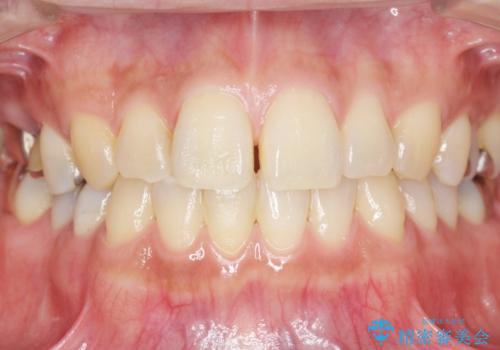

低価格でしっかりとしたインプラント治療 30代男性

- 30代男性

- 5ヶ月

- ¥385,000 (インプラント、アバットメント、仮歯、クラウン) ※税込費用は治療当時の料金となります